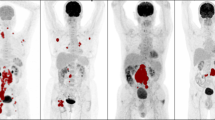

Three experienced (> 10 years) nuclear medicine physicians (A.H., T.V.B., and K.H.) blinded to clinical information except patient age performed visual analysis of images. Observers were asked to rate the following tentatively predictive parameters: (1) prognosis (poor/favorable), (2) tumor volume estimate (eMTV) (in milliliters), and (3) tumor volume (MTVvas) (visual analog score; VAS, 1–9). Observers were asked to restrict the time spent evaluating these parameters to a maximum of 30 s per evaluation in order to reflect the intuitive interpretation of the images. Figure 1 depicts the VAS scale used by our reviewers as well as examples of patients with poor and favorable prognosis. To visually assess prognosis, reviewers were asked to take into account tumor heterogeneity, tumor volume, infiltration into adjoining tissue, extra-nodal spread, and diffuse involvement of, e.g., the pleura or peritoneum.

Metabolic tumor burden assessed on a VAS scale with representative examples of patients graded as 1, 5, and 9 (a). All reviewers used these examples to grade individual cases in the study. b An example of a patient with a poor prognosis based on the widespread peritoneal lymphomatosis, bulky disease, and high metabolic tumor volume. Pointedly, the peritoneal lymphomatosis may be difficult to accurately quantify using semi-automatic tumor delineation tools whereas the severity of disease is readily perceived by visual inspection using a maximum intensity projection FDG PET/CT. c A patient with limited mediastinal disease used as an example of a patient with favorable prognosis